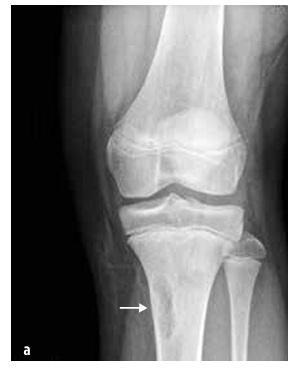

Jóindulatú daganatok

Gyermekkorban gyakrabban fordulnak elő, mint a rosszindulatú daganatok, pl. csontdaganatok (osteoid osteoma, osteoblastoma, eozinofil granuloma), kötőszöveti daganatok (fibrózní dysplazie, neosifikující fibrom (lásd a 7. ábrát)), csontciszták, porcdaganatok (osteochondroma, enchondroma, chondroblastoma) és egyéb (synovialis hemangioma és pigmentos vilonoduláris synovitis).

7. kép

Neosificáló csontfibróma